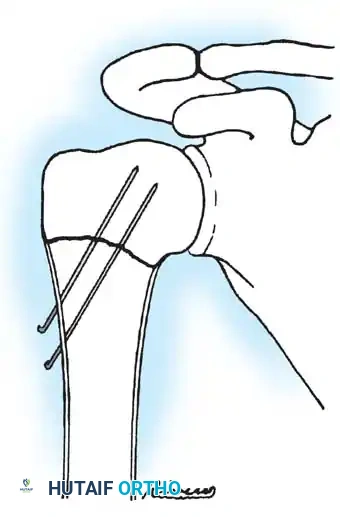

Step 4: Percutaneous Pinning (The Alternative to Spica Casting)

* If the fracture is unstable upon bringing the arm down, percutaneous pinning is highly recommended to allow the arm to rest in a neutral, comfortable position.

* Drive one or two smooth Steinmann pins (typically 2.0 mm or 2.5 mm depending on patient size) through the lateral cortex of the distal shaft, directing them proximally and medially across the physis into the humeral head.

* Neurovascular Warning: Ensure pin entry is lateral and distal enough to avoid the axillary nerve, which courses approximately 5 to 7 cm distal to the lateral acromion.

* Verify pin placement and fracture reduction on both AP and axillary fluoroscopic views.

* Cut the pins beneath the skin to prevent pin-tract infections.

Fig. 33-95 Closed reduction and percutaneous pinning of a proximal physeal separation. Two smooth wires cross the physis to provide rotational and angular stability while minimizing physeal damage.